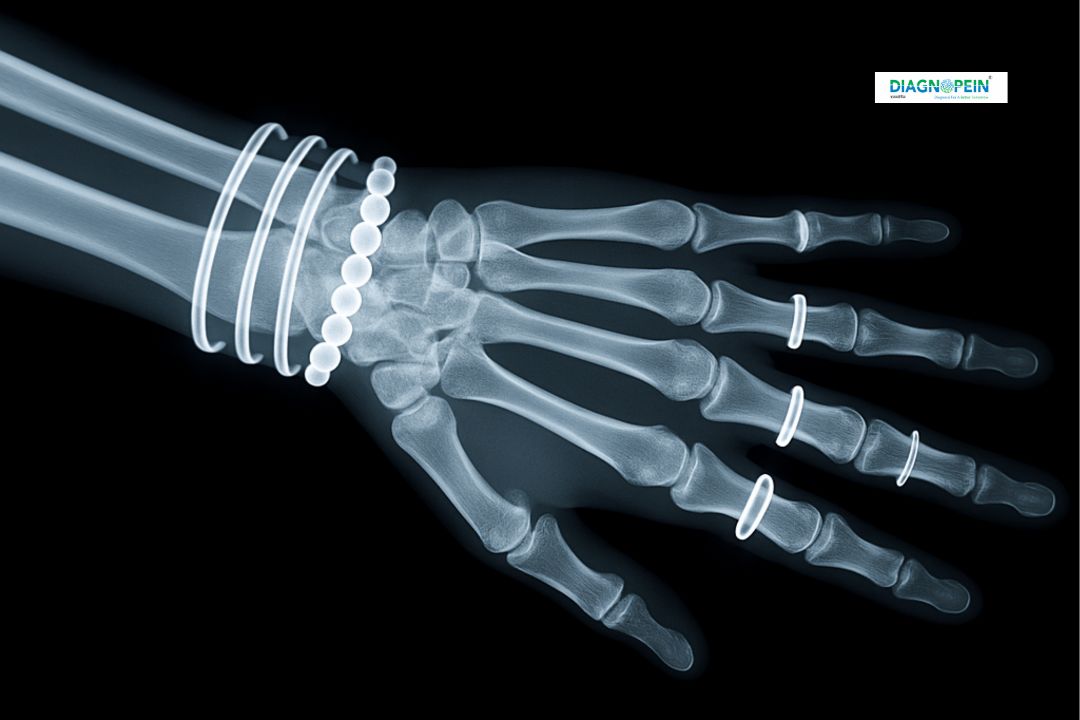

An X-Ray Right Hand AP/LAT is a standard imaging test that captures two distinct views of the right hand – Anteroposterior (AP) and Lateral (LAT). This test helps doctors visualize the bones, joints, and surrounding soft tissues of the hand. At Diagnopein, Karad, we use advanced digital radiography systems to deliver clear, high-resolution images that assist in accurate diagnosis of fractures, dislocations, arthritis, bone deformities, and infections.

X-Rays use a minimal dose of radiation to produce images quickly and painlessly. The AP view provides a front-to-back image, while the lateral view shows the side profile, offering a complete picture of the hand’s bone structure. Our expert radiologists in Karad ensure precise imaging and rapid reporting for better patient care.